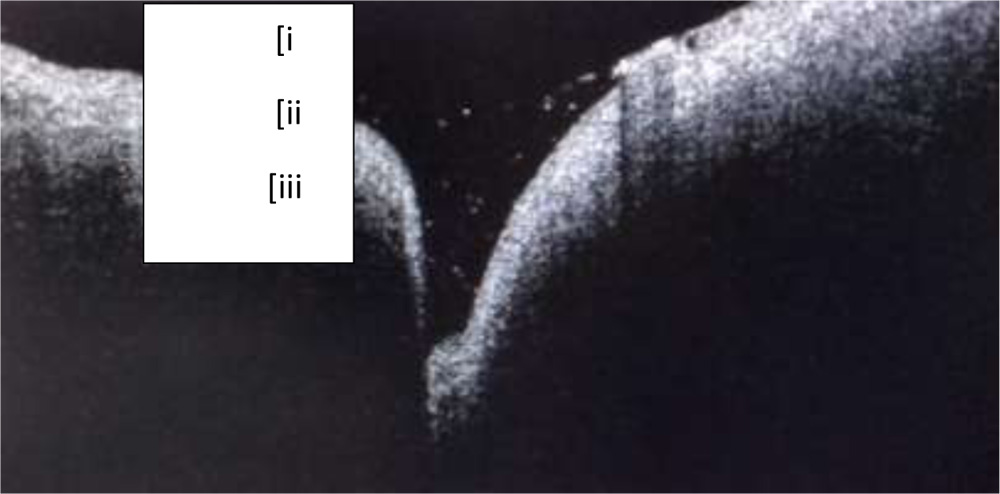

The study included 80 puncta of 40 asymptomatic adults out of which 28 were males and 12 were females. Mean age ± SD was 38.9 ±12.81 years. (median =37.5years).Lower puncta and its junction with vertical canaliculus could be imaged in all cases using SD ASOCT. Three consecutive tissue layers could be identified. Outermost layer was identified as the epithelium. The second layer was hyperreflective compared to the first layer with as smooth interface in between. This layer corresponded to fibrous tissue layer. The third layer was hyporeflective compared to the second layer with an irregular interface in between. This layer corresponded to muscle of Riolan (Fig2)

Fig 2: i) Outermost epithelial layer ii) Fibrous tissue layer hyperreflective in comparison to epithelium with a smooth interface in between iii) Muscle of Riolan hyporeflective in comparison to ii) with an irregular interface. Tear film with debris can be seen as punctal content